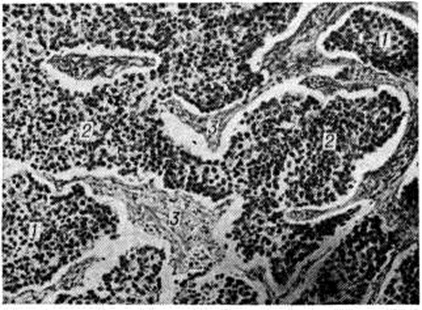

Микроскопическая картина дисгерминомы яичника: характерны однотипные индифферентные герминогенные клетки, образующие ячейки (1) и поля (2), разделённые соединительнотканными прослойками (3), инфильтрированными лимфоцитами.

Микроскопически Дисгерминома состоит из крупных круглых или полигональных клеток с большими ядрами, содержащих гликоген и образующих ячейки и поля, разграниченные соединительнотканными прослойками, которые обильно инфильтрированы лимфоцитами (рисунок). Иногда видны многоядерные гигантские клетки типа Пирогова — Лангханса. Цитоплазма клеток Дисгерминома содержит щелочную фосфатазу. Опухоль рано метастазирует по лимфатический, и кровеносным сосудам. Морфологически Дисгерминома идентична атипическим тератомам эпифиза мозга (шишковидного тела) и гипоталамуса.